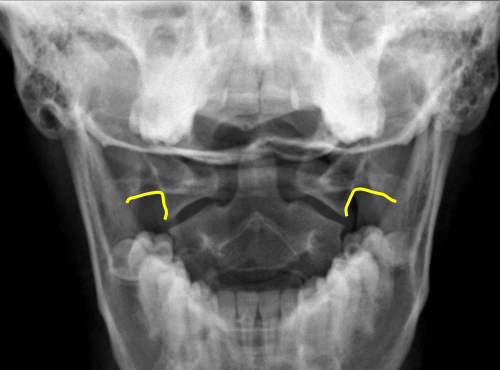

yellow

Occipital condyles

blue

Foramen magnum

C1 TVP/ lateral mass junction